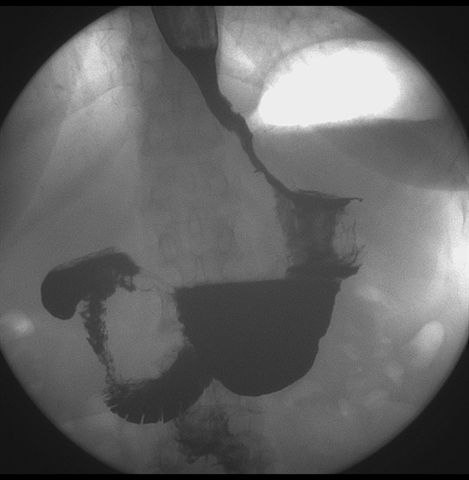

标题: X6872:F,69y,胃部不适。

胃窦至幽门段胃壁僵硬,扩张受限,局部纠集粘破坏,呈杵状。提示溃疡癌变可能性大。

胃窦癌可能性大,建议胃镜活检。钡剂太稀,吃的有点多。

支持考虑胃窦癌可能,胃内滞留液太多,胃窦部僵硬。

胃窦部见钡池影,局部粘膜紊乱,纠集呈杵状改变,胃壁扩张受限,胃窦癌可能性大,建议胃镜检查.

胃窦部管腔扩张度较差,形态略有改变,胃窦粘膜显示欠佳,胃窦部占位可能性大,结合胃镜活检。

北京肿瘤医院胃镜诊断皮革胃。